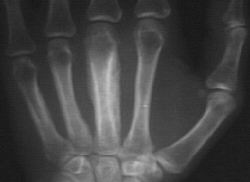

2. The following can be associated with the pictures above:

Refer to this picture for question 4. |

4. Systemic association include:

5. The child may have the following additional signs: